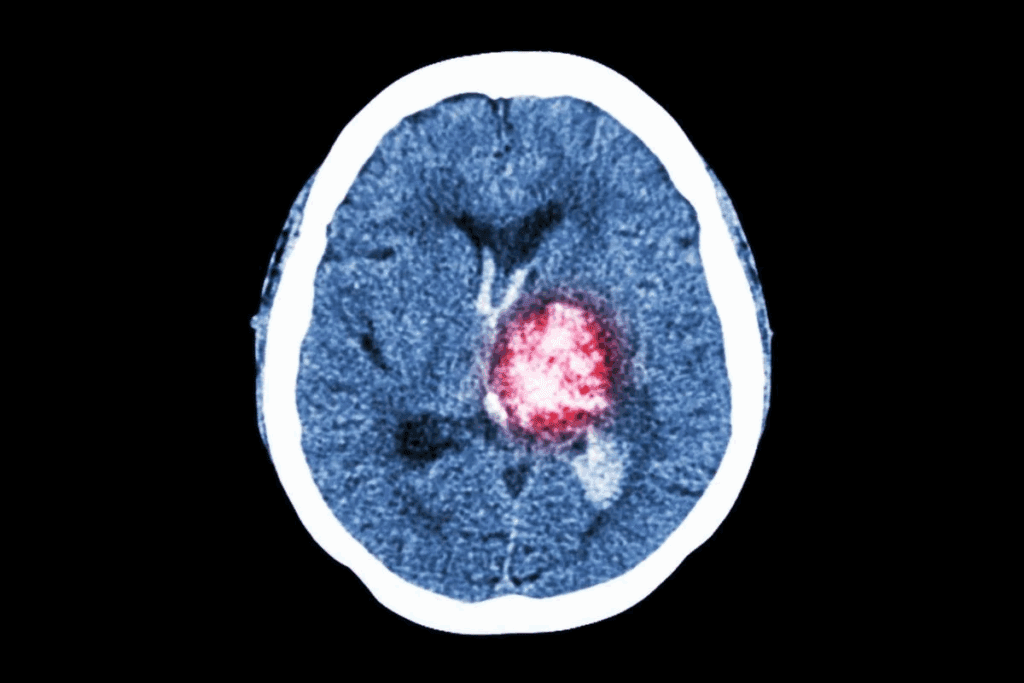

Anatomical Considerations

The location of a tumor affects its curability. Tumors in vital or hard-to-reach areas, like the brainstem or pancreas, are tough to treat.

Diffuse intrinsic pontine glioma (DIPG) is a brain tumor that can’t be surgically removed. Its location in the brainstem limits treatment options.

Diffuse Intrinsic Pontine Glioma (DIPG)

DIPG is a rare and aggressive brain tumor that mainly affects kids. It grows in the pons, a key part of the brainstem. This makes treating it very hard.

Challenges in Pediatric Brain Tumors

DIPG is a very tough brain tumor for kids, with a short survival time. It’s hard to treat because of its location, how fast it grows, and the age of the patients.

Because of its location in the brainstem, surgery is not an option. It would harm important brain areas. So, treatments mainly include radiation and chemotherapy.

Anatomical Barriers to Treatment

The brainstem, where DIPG grows, controls essential functions like breathing and heart rate. This makes treating it very tricky.

Doctors must find ways to target the tumor without harming the brain. But DIPG spreads, making it hard to know where to treat.